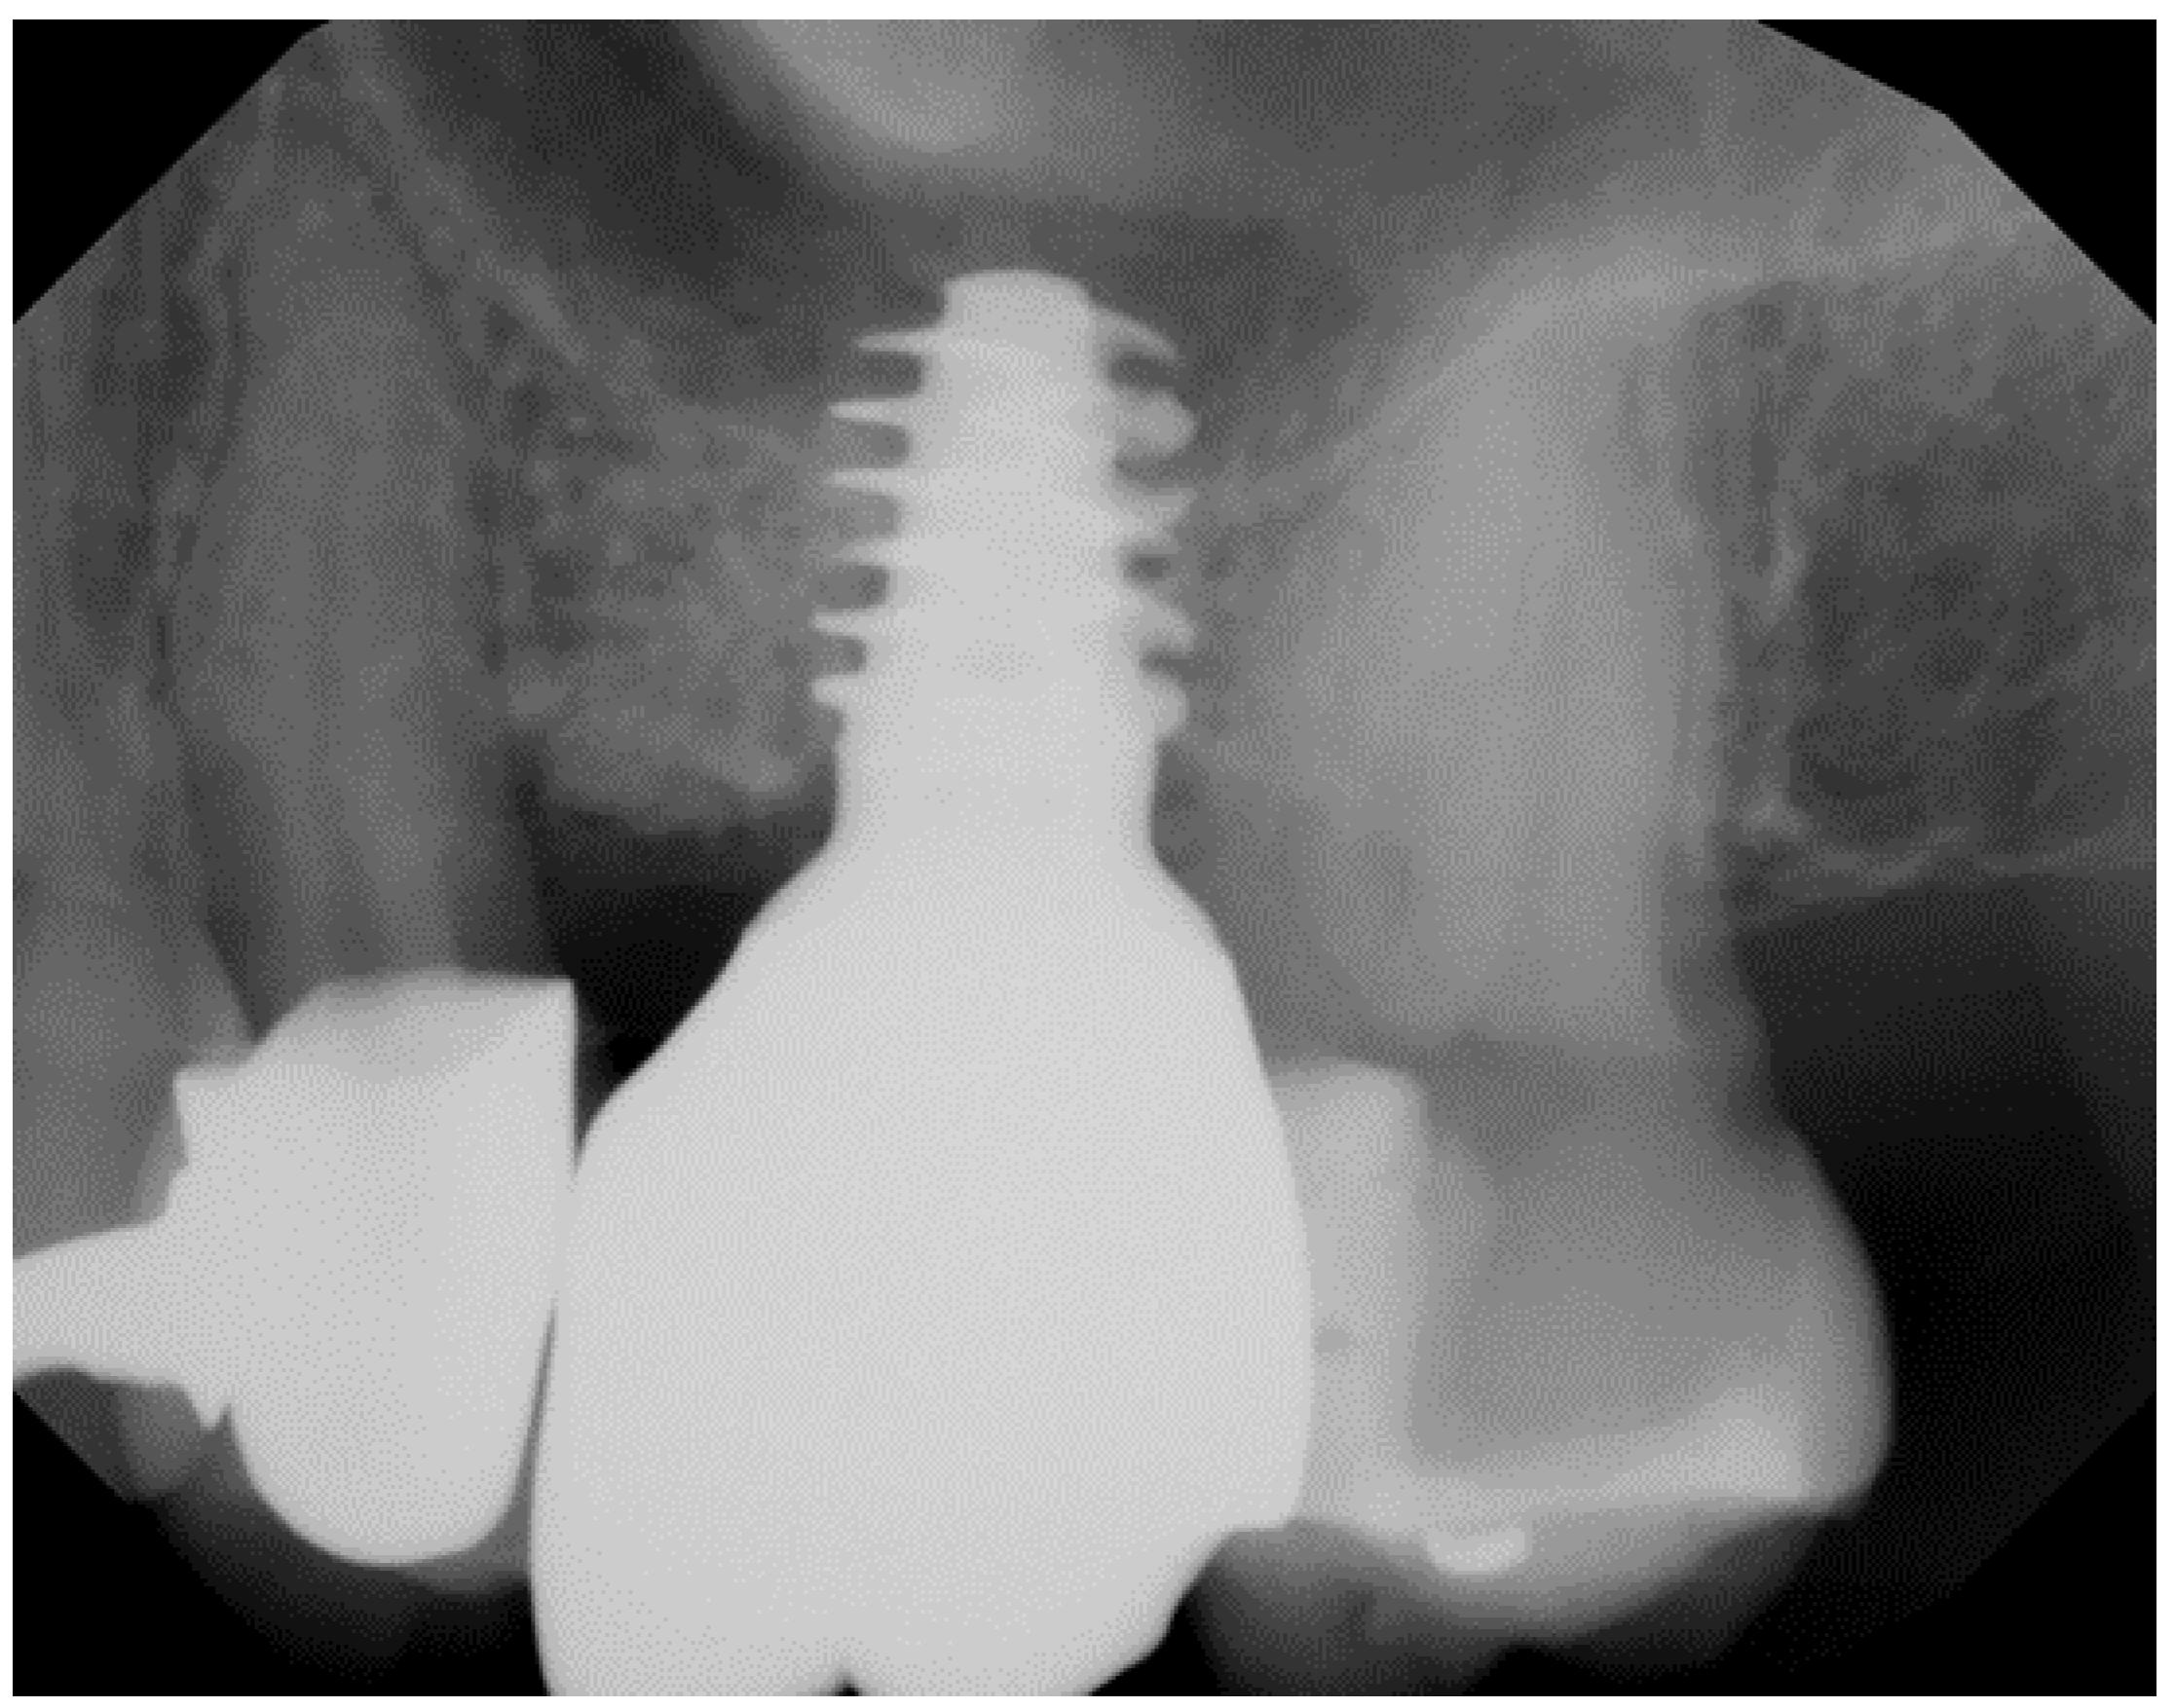

- Pirker, W.; Wiedemann, D.; Lidauer, A.; Kocher, A.A. Immediate, single stage, truly anatomic zirconia implant in lower molar replacement: A case report with 2.5 years follow-up. Int. J. Oral Maxillofac. Surg. 2011, 40, 212–216. [Google Scholar] [CrossRef]